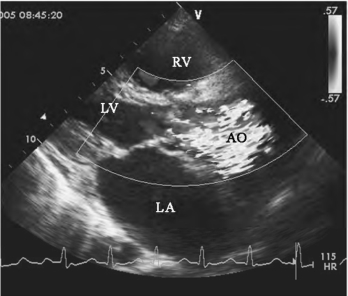

(3)彩色多普勒显示从主动脉瓣口向升主动脉内走行的蓝色为主的五彩镶嵌射流(图13-13)。

图13-13 主动脉瓣狭窄彩色多普勒血流图(见彩图12)

胸骨旁左室长轴观主动脉瓣开放受限,彩色多普勒血流图显示主动脉瓣上蓝色为主、五彩镶嵌射流